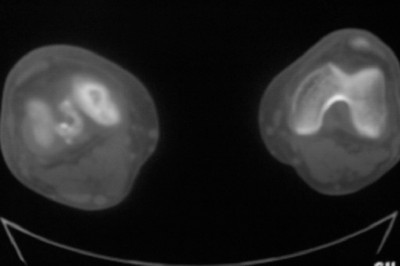

标题: CT8024:会诊!!!男 60 岁 双漆关节疼痛半年,进行性加重 [打印本页]

患者男 60 岁 双漆关节疼痛半年,进行性加重.

左侧股骨下端骨梗死

右股骨内髁关节面下多个不规则小囊变,边缘有明显硬化边,.......考虑: 1.关节面下骨囊变.  2.类风湿关节炎?   3.血友病?

右侧髁间隆突变尖,软骨下假囊肿形成,结合病人年龄较大,首先考虑退行性骨关节病。关节周围软组织未见明显异常,病人单单一双膝关节出现症状,不太支持类风湿性关节炎,可结合化验室检查。